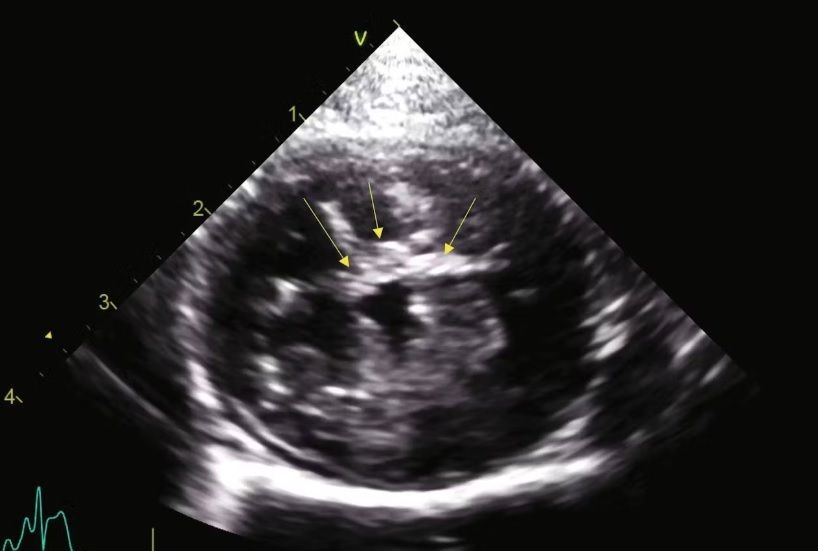

- L’échocardiographie : il s’agit de l’échographie du cœur. Cet examen est fait par des spécialistes.

La maladie cardiaque la plus fréquente chez le chat (dans 75% des cas) est une myocardiopathie hypertrophie ou CMH : la paroi du cœur s’épaissie, entrainant une modification dans le flux sanguin. La dépister est essentielle, car cette maladie peut décompenser dans 30% des cas et entrainer des symptômes extrêmement graves et dangereux pour la santé de votre chat.